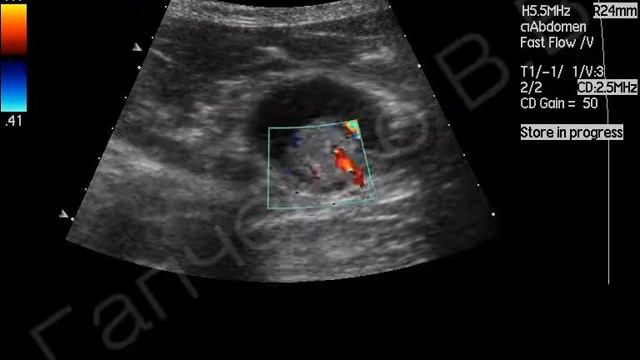

На узи есть полип

На узи есть полип 115 фото